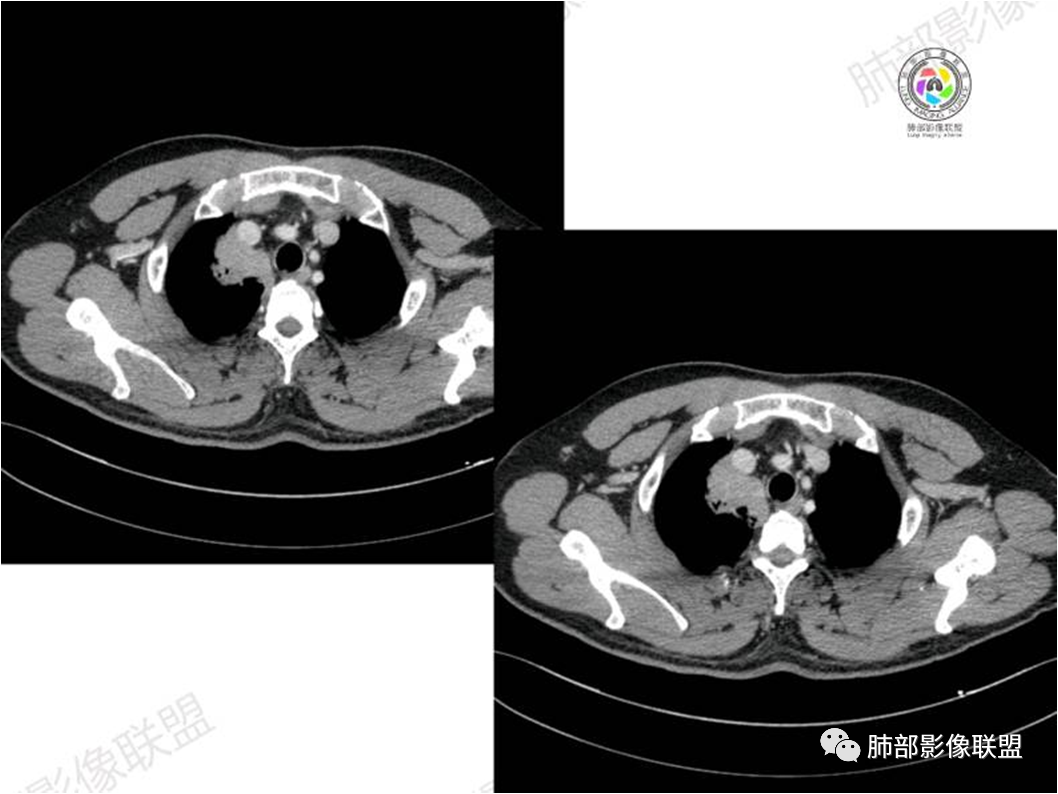

右肺上叶纵隔胸膜侧一实性肿块,与纵隔胸膜宽基底相连,局部脂肪间隙消失,形态欠规则,内部可见多个小空泡,平扫密度尚均匀,增强后可见点条状强化,内部穿行血管,周围肺组织干净,纵隔淋巴结略肿大,男性44岁,只有咳嗽,考虑恶性肿瘤,腺癌,鳞癌。鉴别结核,OP,炎性假瘤。

中年男性,右肺上叶纵隔旁软组织肿块,边缘膨隆、毛糙,可见多发分叶,支气管穿行,部分截断,增强后密度欠均匀,纵隔内见多发小淋巴结,首先考虑恶性,腺癌,鉴别淋巴瘤

⑥肺门及纵隔淋巴结肿大少见;

⑦胸腔积液少见且多为良性,与淋巴管或静脉阻塞有关,本组出现率约26%;

⑧邻近胸膜多无增厚,部分胸膜下见清晰脂肪或少许积液可能具有一定特征性,既往国内外研究尚未报道此征象,本文认为其病理学基础可能为肿瘤细胞生长缓慢,多为间质淋巴瘤样浸润而不破坏脏器解剖结构,肺泡塌陷及周围纤维组织增生,可能致病灶牵拉邻近胸膜有关,这不同于文献;报道的机化性肺炎致邻近胸膜多条状水肿、增厚,此征象有助于二者的鉴别。